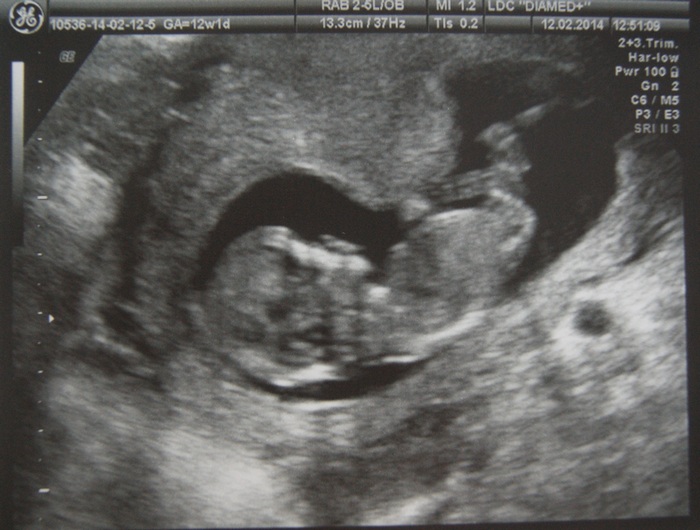

Результаты: УЗИ, КТГ, доплера, скринингаИ вот он наш долгожданный скрининг! Как же меня трясло перед кабинетом...думала поседею от переживаний... И вот показали нашего малыша! Он кажется не реально большим! Животика еще нет, бер-ть ни как не чувствую, а тут такого человечка показывают))) Давай там переворачиваться, шевелиться

Врач попался молчаливый, так долго что-то высматривал, а я уже начала бояться этого молчания... И только под конец выдал что всё в норме, ТВП - 1,9мм, носик есть, ручки и ножки есть, и остальное в норме

И вот наш малышастик